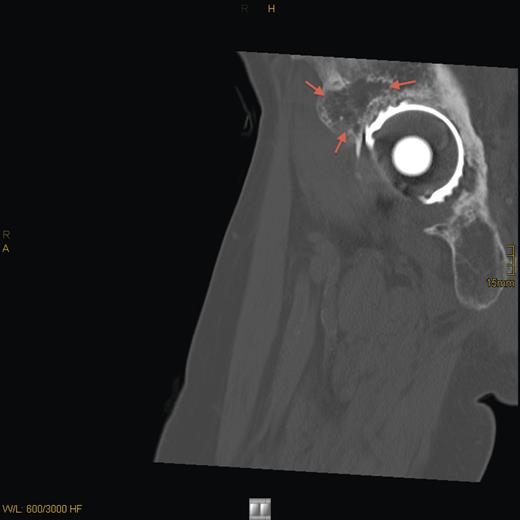

Magnetic resonance imaging (MRI) and computed tomography (CT) scanning showed a destructive lesion, 5 cm in diameter, in the right os ilium and obturator internus muscle (Fig. 1). FGF-23 levels were significantly high and an octreotide scan was positive for radionuclide uptake in the right acetabulum. CT-observed biopsy of the right acetabulum was performed, and histological analysis revealed a benign phosphaturic tumor (PHT) of mixed connective tissue type.

Sagittal T2-weighted, fat-suppressed contrast-enhanced MRI demonstrating the tumor lesion (5 cm in diameter) in the right acetabulum (arrows) 8 years prior to presentation.